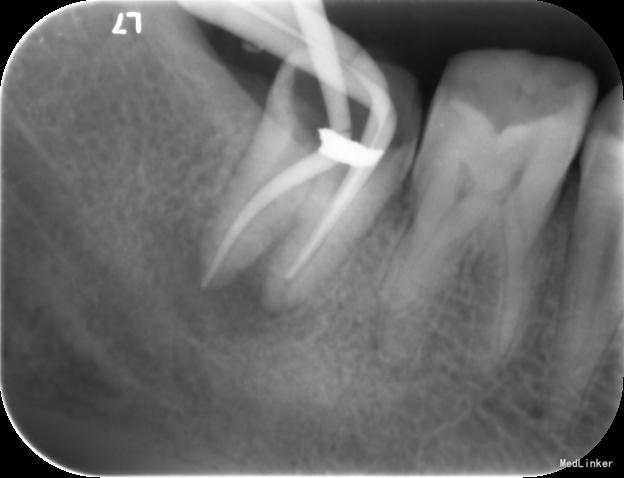

检查:右下7髓腔开放,可见髓腔内食物残渣及部分银汞充填体,叩痛(++), 冷热刺激无反应,松动1度,牙体已制备,牙合龈距离低,X线片示根尖区密度减低区。

诊断:难治性根尖周炎 治疗计划:告知患者病情,治疗难度及预后,拟行根管再治疗,但术后效果不确定,如若不理想拟需行根尖手术甚至牙拔除术。患者知情同意,并要求尽量行保留牙齿治疗。 处置:第一次 揭全髓顶,去腐,疏通根管,测量工作长度,机扩预备至S1,超声荡洗,激光消毒,封CP球。口服抗炎药。一周后复诊。 第二次 复诊无叩痛,暂封物在。去除暂封物,双氧水和盐水交替冲洗,EDTA伴随下根管预备至F2,超声荡洗,激光荡洗+激光消毒,封氢氧化钙。两周后复诊。 第三次 复诊无叩痛,暂封物在。 去除暂封物,双氧水和盐水交替冲洗,EDTA伴随下根管预备至40号,超声荡洗,激光荡洗+激光消毒,封vitapex,玻璃离子体充填。拍X线片。一月后复诊。 第四次 复诊无疼痛 旧充填体在 拍X线片可见根尖阴影变小,故未行任何治疗,嘱患者1月后再次复诊。 第五次 复诊无疼痛 旧充填体在 拍X线片未见根尖阴影变小,故去除旧充填体,冲洗,去除vitpex,根管再次预备,双氧水和盐水交替冲洗,超声荡洗,激光荡洗+激光消毒,封氢氧化钙。两周后复诊。 第六次 复诊无疼痛 去除暂封物,冲洗,见根管内无渗出,试尖,超声荡洗,激光荡洗和消毒,干燥,AHplus糊剂和热牙胶充填,糊剂超填,玻璃离子体充填。请口腔外科医生会诊是否可行根尖手术,外科医生建议因手术难度大,且病变与下颌神经管接近,建议随诊观察,暂不考虑行根尖手术。必要时考虑意向性牙再植术或者牙拔除术。嘱患者1月后复诊,结果患者失诊。